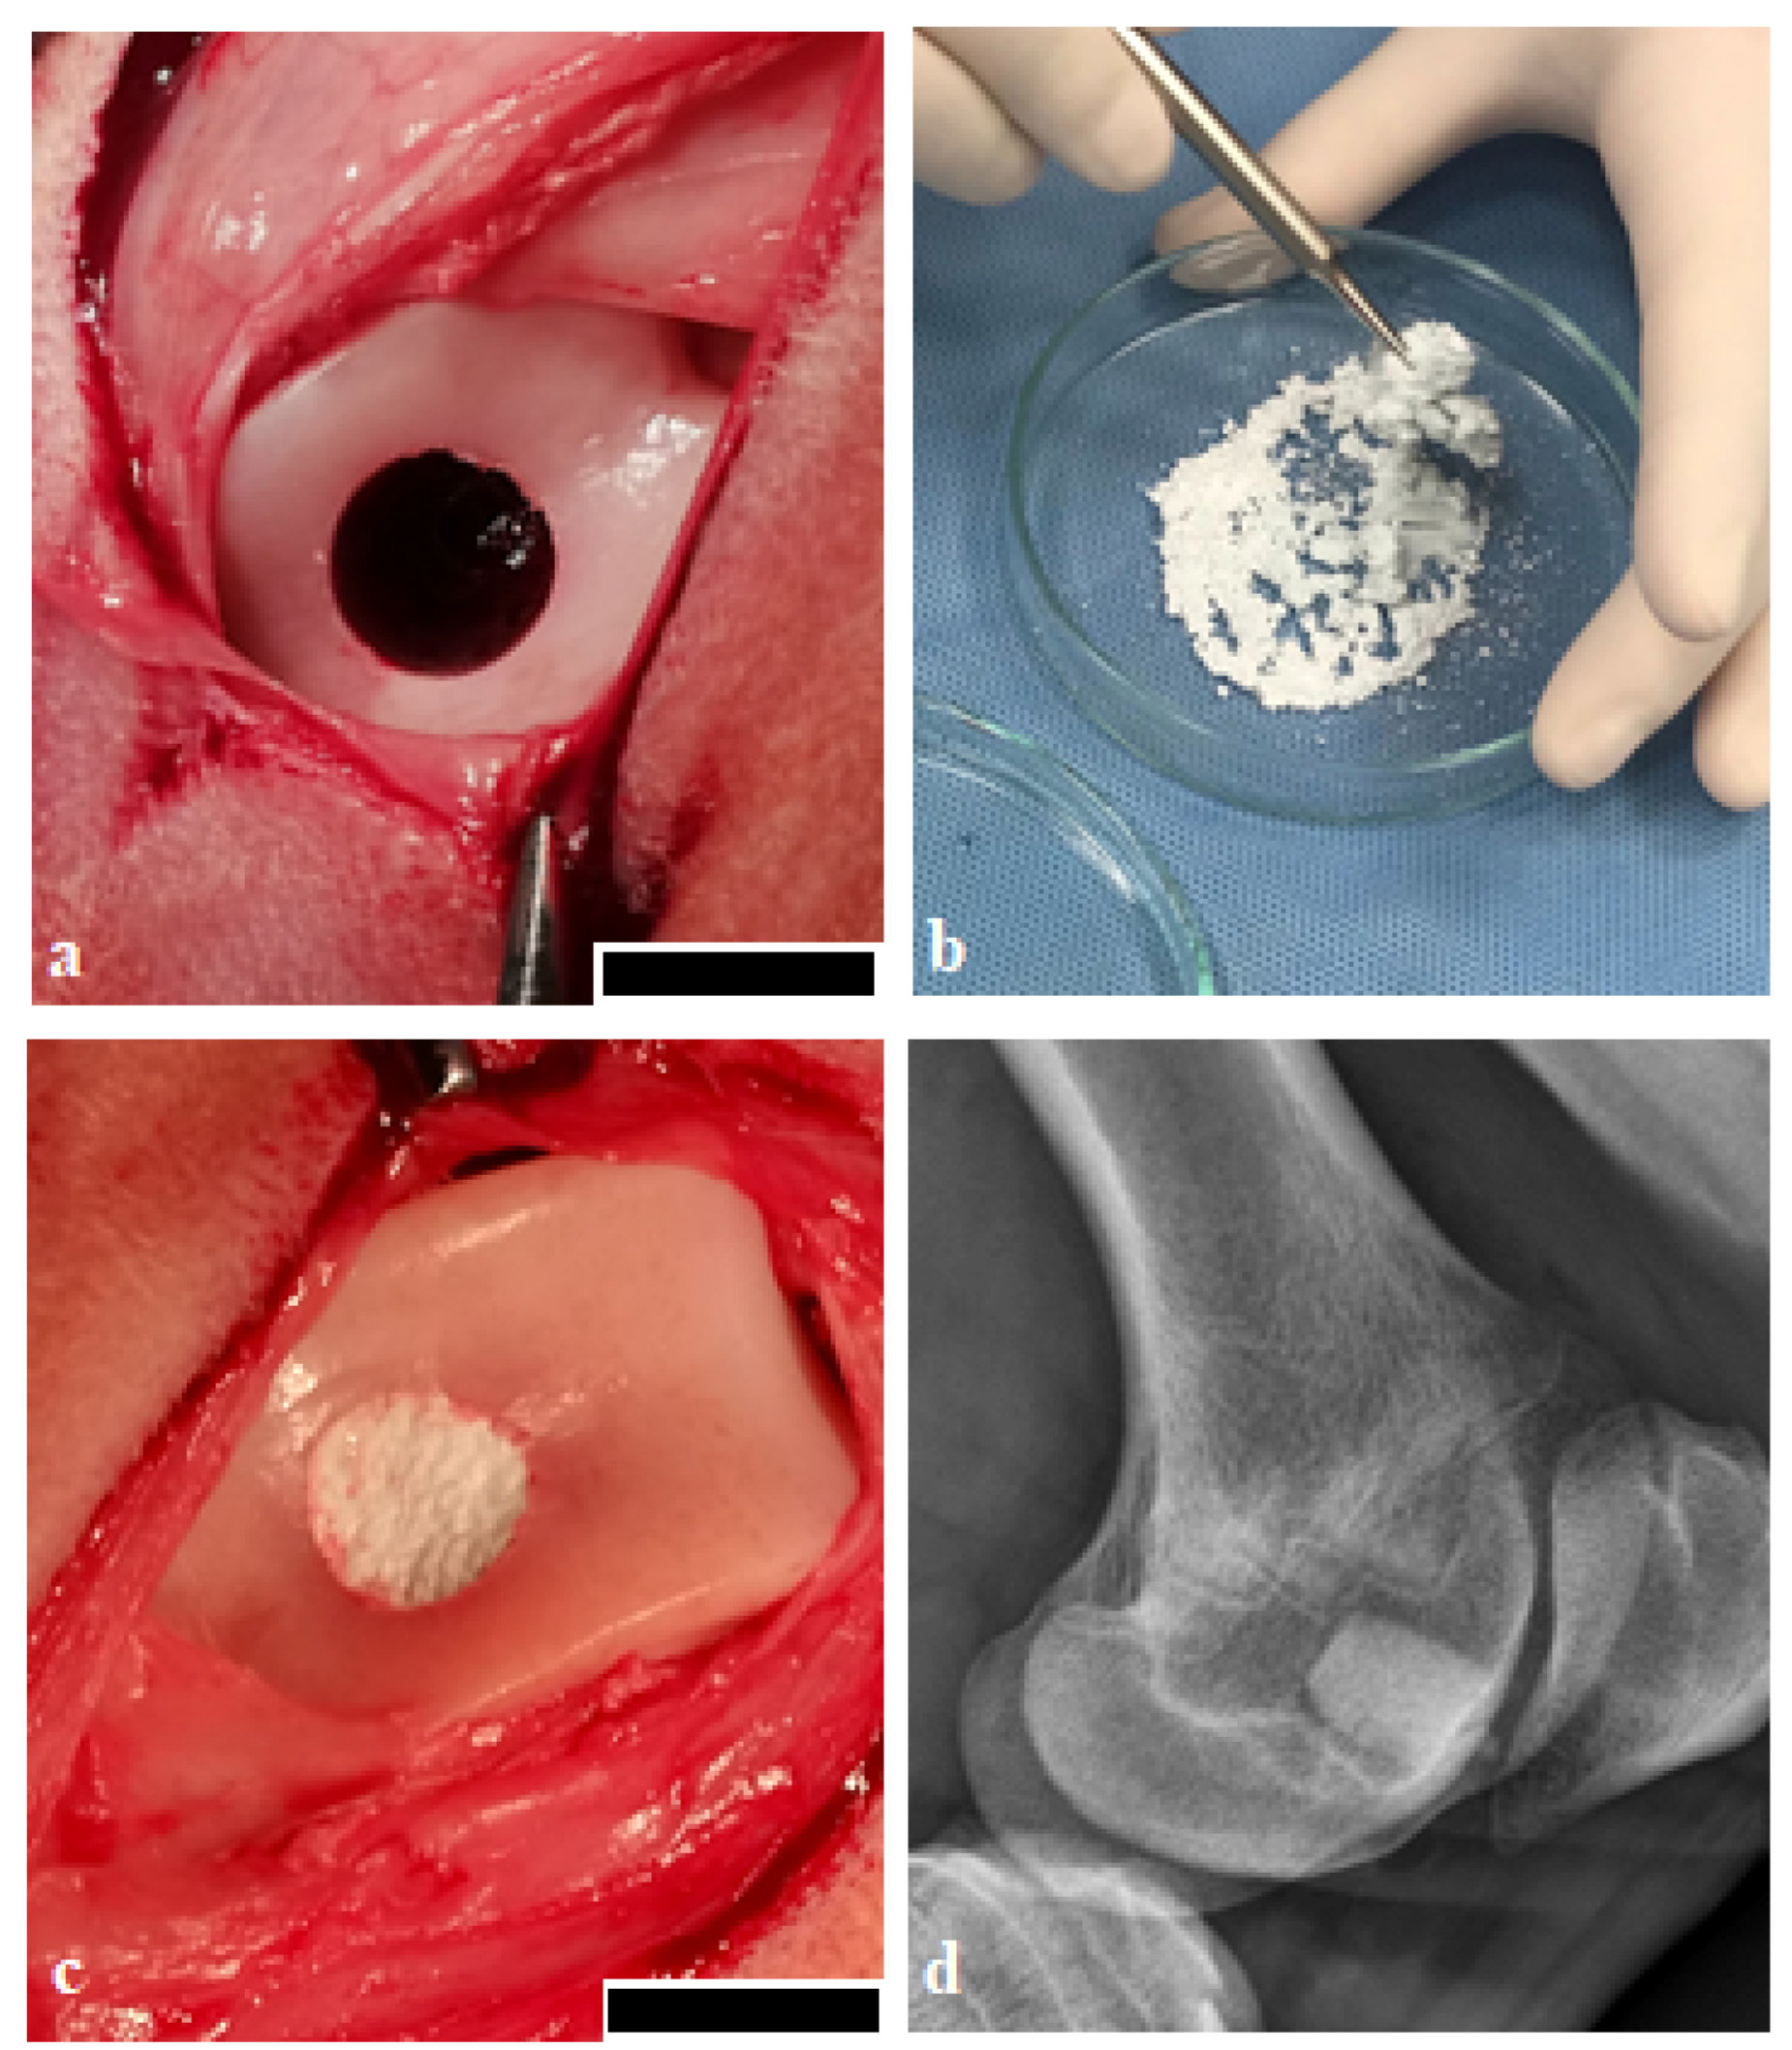

4. Materials and Methods

4.2. Animals, Surgical Procedure, Postsurgical Period

4.3. Macroscopic Analysis